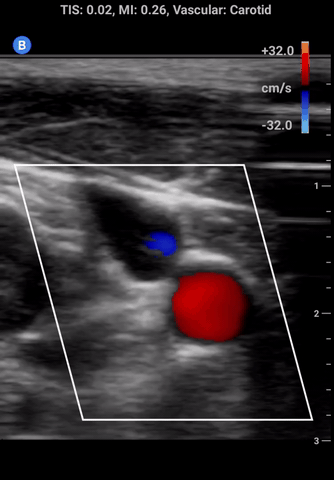

Colour doppler: in this mode a small window appears on the screen that detects the velocity and direction of flow which is represented using colour. At the side of the screen a colour scale will appear; the colour on top represents flow towards the probe and colour on the bottom away from the probe.